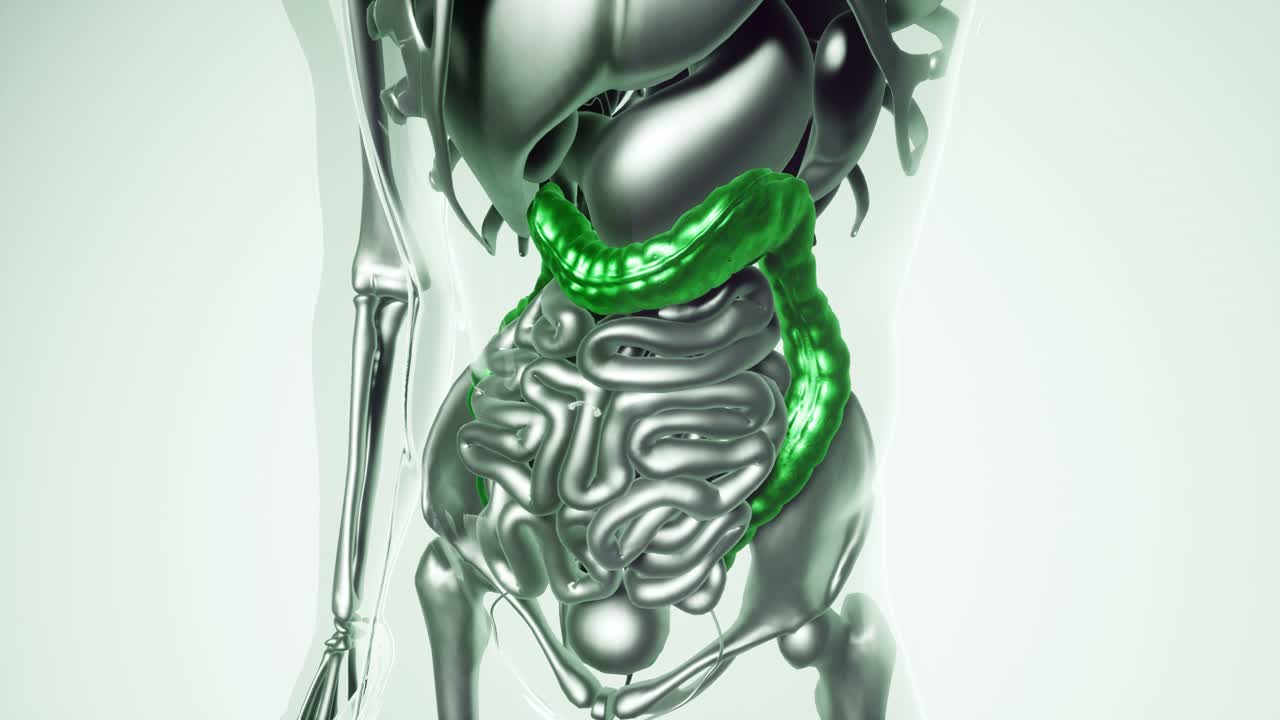

rotación en bucle del tracto intestinal con efecto holográfico, renderización en 3d.

modelo de colon humano con todos los órganos

Futuristic video concept of the human digestive system

Detailed 3D Visualization of the Human Digestive System: Exploring the Anatomy and Functionality of Organs from Stomach to Intestines